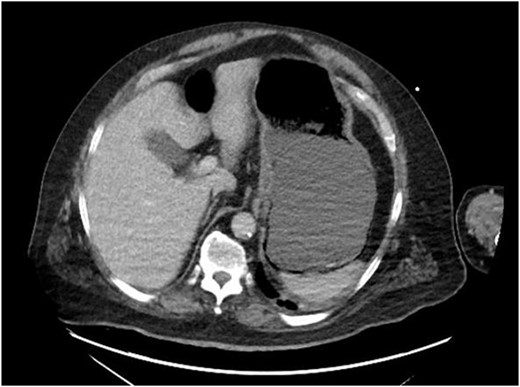

On evaluation, the patient was afebrile, tachycardic to 107 bpm, with BP 112/63 and RR 21. On exam, he appeared diaphoretic and had left upper quadrant tenderness without rebound or guarding. He was otherwise alert and oriented. His white blood cell count was 22.5 with 13.1 bands, and lactate of 6.2, which improved with IV fluid resuscitation. Computed tomography (CT) abdomen and pelvis demonstrated pneumatosis of the proximal gastric wall (Fig. 1), and mild portal venous gas. He was started on antibiotics and antifungals; a nasogastric tube was placed for decompression, and he was started on parenteral nutrition; however, he failed to improve clinically, with continued abdominal pain and tenderness, and persistent tachycardia. A repeat CT after 5 days of treatment redemonstrated gastric wall pneumatosis (Fig. 2), though with resolution of the portal venous gas.

Repeat CT of the abdomen and pelvis: decompression of the stomach with persistent gastric pneumatosis.